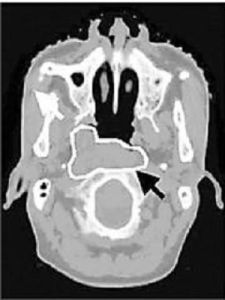

檢查:鼻咽癌好於咽隱窩及鼻咽頂後壁,可用間接鼻咽鏡或纖維鼻咽鏡進行檢查。早期病例可見局部黏膜粗糙不平,並有小結節及肉芽樣腫物。腫瘤逐漸發展可呈現為菜花型、結節型、潰瘍型或黏膜下型等不同臨床類型。 X線顱底拍片有助於了解骨質有無破壞。CT掃描可顯示鼻咽黏膜變化,對早期鼻咽癌的診斷頗有幫助。診斷 首先在於思想重視,遇有上述症狀者,應仔細檢查鼻咽。對可疑病例須及時施行活檢,必要時可重複進行。活檢取材有經鼻腔和經口腔二種方法。細胞學塗片檢查可發現早期潰瘍浸潤病變。由於鼻咽癌病人的EB病毒抗體遠較其他惡性腫瘤及正常人高,病毒殼抗原——免疫球蛋白A(VCA—IgA)抗體測定已漸被用為普查篩選本病及治療後隨訪監視的手段。